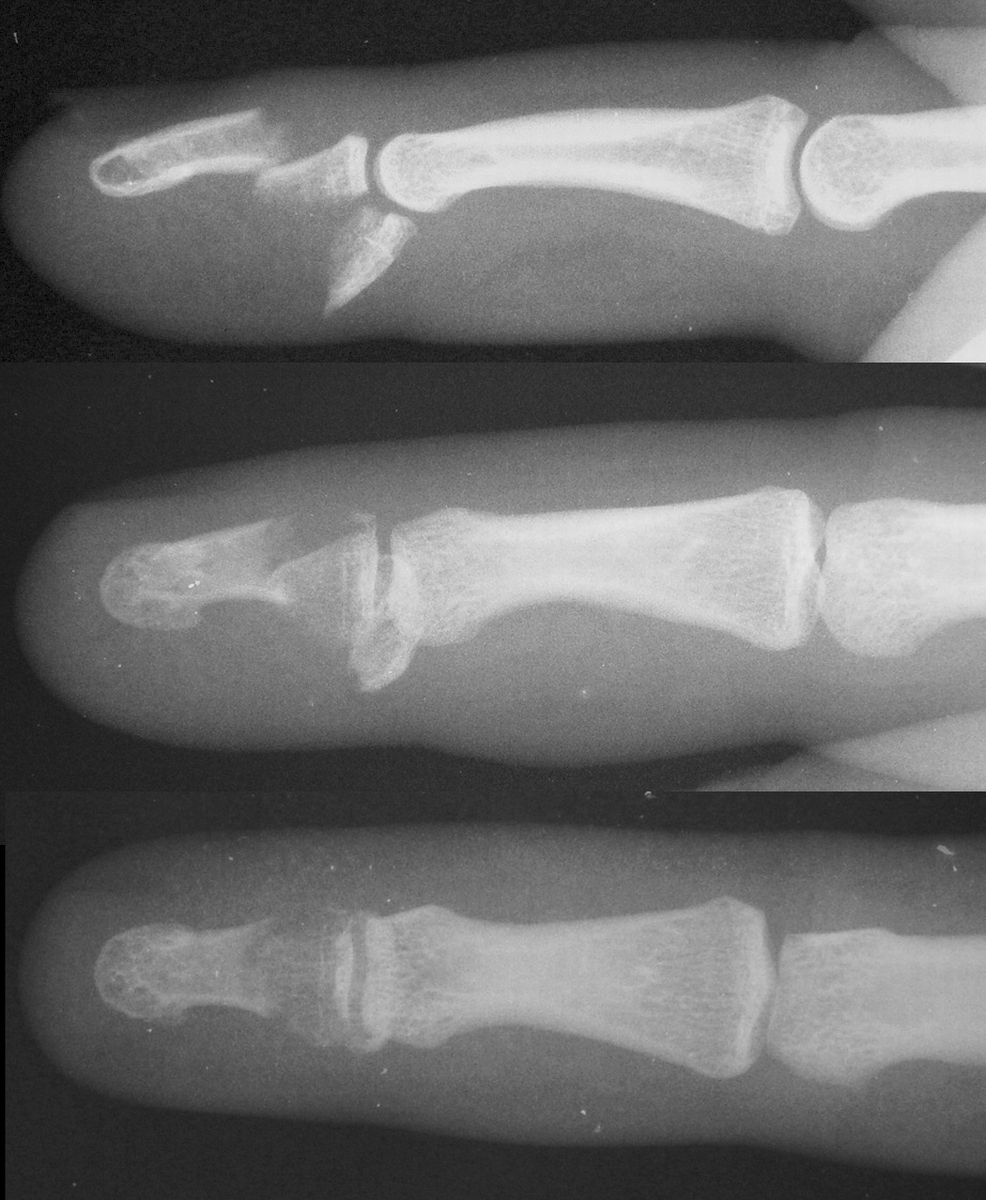

| One week postop. |

| Three months postop, after removal of prominent pins in the office. |

| Case 2. This patient sustained a closed displaced distal phalanx base fracture with dorsal-palmar split and dorsal subluxation of the larger fracture fragment. |

| This was managed with two wires - a cerclage wire, passed over the dorsum in a subperiosteal plane, and an interfragmentary palmar wire. The profundus tendon was found to have avulsed from the palmar fragment, and the tendon was reattached with sutures passed around the palmar component of the cerclage wire. A temporary longitudinal interfragmentary pin was also used (not shown). |